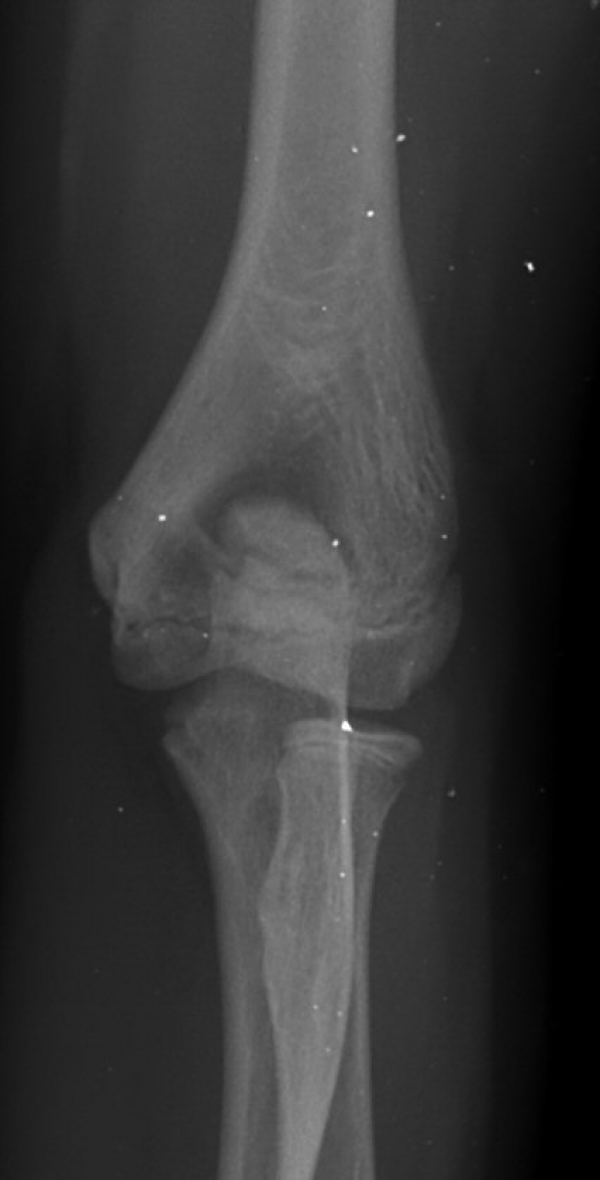

ÆÈ²ÞÄ¡ ³»»ó°ú ¿ÜÃø¿¡ ¹Ì¼¼ÇÑ °ñÆíÀÌ °üÂû µÊ(±×¸² 7).